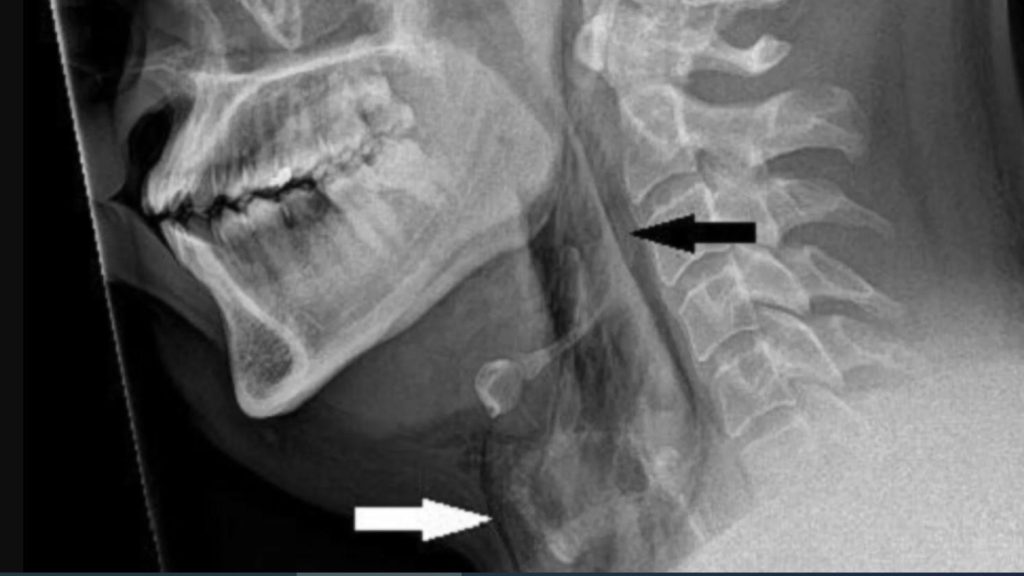

وكشفت عمليات المسح بحسب (RT) عن تمزق في القصبة الهوائية، وفي الحالات الشديدة، يمكن أن تؤدي تمزقات القصبة الهوائية إلى تضييق المسالك الهوائية، ما يسبب مشاكل في التنفس تهدد الحياة.

وقال الأطباء: “نشتبه في أن القصبة الهوائية مثقوبة بسبب التراكم السريع للضغط في القصبة الهوائية أثناء العطاس مع أنف مسدود وفم مغلق”.